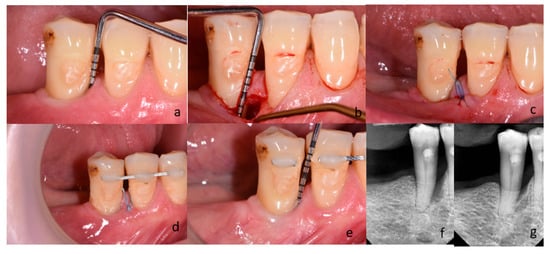

2.3. Clinical Examinations, Surgery, and Postoperative Care